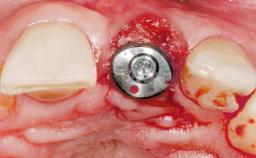

Immediate Flapless Placement of an Implant in a Maxillary Left Central Incisor Site

A 42-year-old female patient was referred to our clinic at the School of Dentistry of the University of São Paulo in November 2004, presenting a deficient restoration in the upper left central incisor. The clinical examination revealed no gingival retraction or any signs of gingival inflammation and, therefore, previous periodontal treatment was not considered. The patient presented a high lip line at full smile and a thin tissue biotype. This combination characterized a high-risk situation from an anatomic point of view, which required careful preoperative planning and cautious surgical execution.

Type of Implants One-Piece

Placement Protocol Immediate implant placement

Socket Morphology Single-root socket

Socket Integrity Sufficient, with intact bone walls

Bone Volume Sufficient, with intact walls